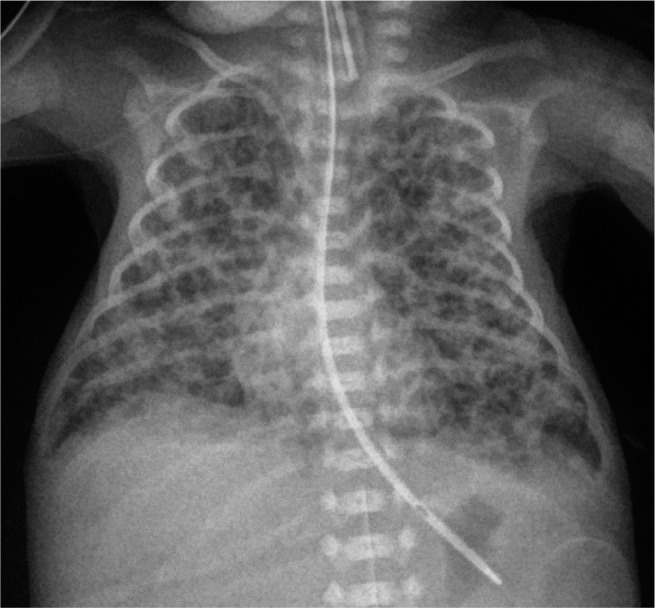

Case report: We present a case of an extremely preterm infant with persistent PTX who was successfully treated with fibrin glue. In addition, we present a two-and-a-half-year corrected age follow-up focusing on respiratory problems, motor development and sensory organs. Furthermore, we touch upon the related ethical issues.

Conclusions: Fibrin glue should be used to treat persistent PTX even in an extremely preterm infant. No adverse effects were observed. At the two-and-a-half-year corrected age follow-up, despite severe bronchopulmonary dysplasia development, no serious pulmonary problems were observed. However, the child's development is uncertain. This situation raises important ethical issues concerning saving the lives of infants at the limit of viability.